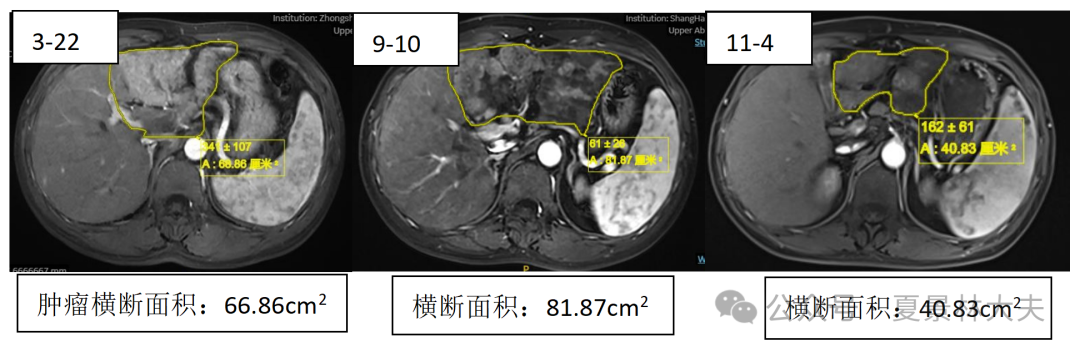

MRI提示病灶范围较前缩小(图5,同一截面,3月份肿瘤横断面面积66.86cm2,9月份81.87cm2,肝肿瘤内科第4次介入治疗后11月40.83cm2);病人的体感也明显好转。